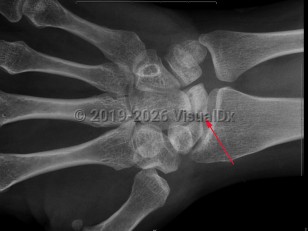

Avascular necrosis